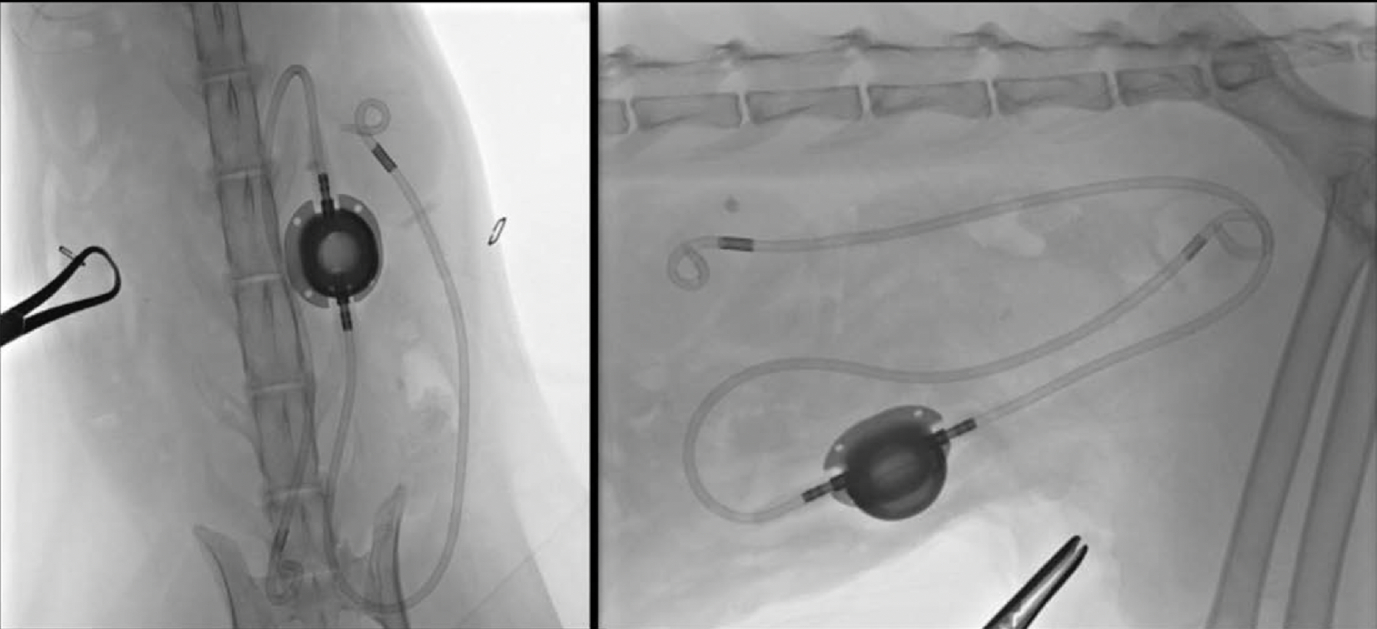

Een SUB is een medisch implantaat dat wordt gebruikt bij katten en honden met een ureter obstructie. Het bestaat uit 3 onderdelen:

• een katheter die in de nier wordt geplaatst (de nefrostomie katheter),

• een blaaskatheter en

• een verbindstukje (de “companion of Swirl port”) dat onderhuids de nefrostomie en cystotomie katheters met elkaar katheter verbindt.

Tijdens een ventrale laparotomie wordt onder fluoroscopische of echografische begeleiding een katheter in het nierbekken geplaatst. Het is heel belangrijk dat deze katheter correct wordt geïmplanteerd om complicaties te voorkomen Daarna wordt er een katheter in de blaas aangebracht. De katheters worden verbonden met een onderhuids verbindingsstukje, de zogenaamde “swirl of companion port”. Door middel van de companion port kan het hele systeem gespoeld worden en kan er urine afgenomen worden voor kweek. Ook wordt tijdens de operatie nauwkeurig gecontroleerd dat er geen lekkage is rond de katheters.